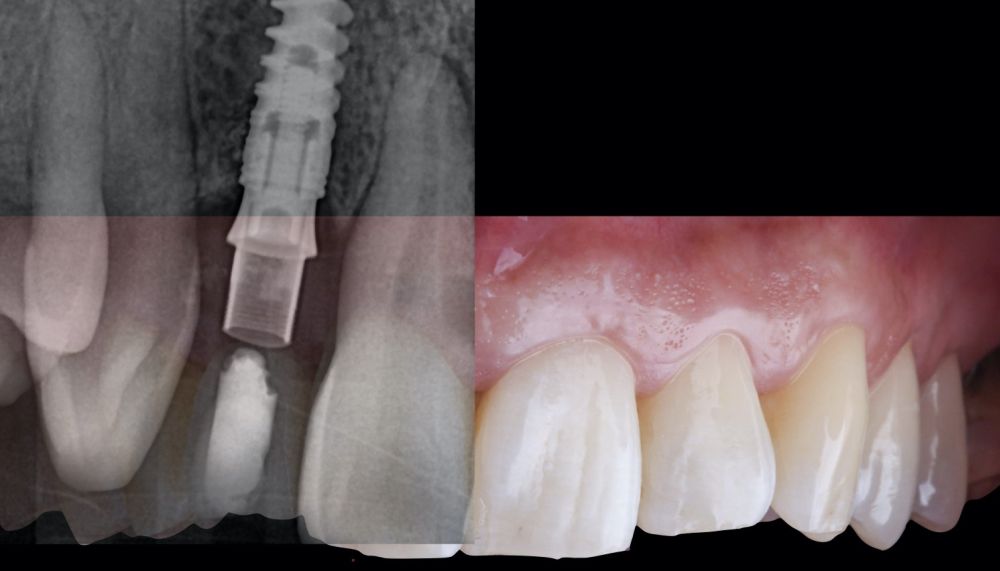

1.2 Treatment

• Phase I: atraumatic extraction of the root remnant 1.2 was performed, followed by curettage of the granulation tissue. Subsequently, the alveolus was filled with an inorganic bovine bone graft (0.25–1mm) combined with autologous platelet- and leukocyte-rich fibrin. Finally, the edges were approximated and sutured with four simple stitches from the vestibular mucosal margin to the palatal aspect. Subsequently, the patient continued using her removable partial denture as a provisional restoration (Figure 1).

* Phase II: healing proceeded without complications. After 5 months from the alveolar preservation surgery, guided implant surgery was planned at position 1.2 (Figure 2). For this purpose, a DICOM file from cone beam computed tomography (CBCT) and an STL file obtained from scanning with an intraoral optical scanner were used. Using this information, a dental support surgical guide was fabricated (Figure 3). The surgical guide was anchored onto the teeth and guided the preparation of the implant bed and the placement of the implant. The guided surgery technique consisted of flap surgery, preparing and inserting the implant (3.5 x 11.5 mm) according to the standardised Nobel Active® guided surgery protocol (Nobel Biocare AB, Gothenburg, Sweden). Once implant 1.2 was placed,a gingival graft composed of epithelium and connective tissue from the palatal masticatory mucosa was obtained. Subsequently, the superficial epithelial layer of this graft was deepithelialised extraorally using a 15C scalpel blade in order to obtain a connective tissue graft from the underlying layer18.

The de-epithelialised graft was inserted and

positioned buccally and occlusally using horizontal mattress sutures with 5-0 non-resorbable suture (Figure 4)19.